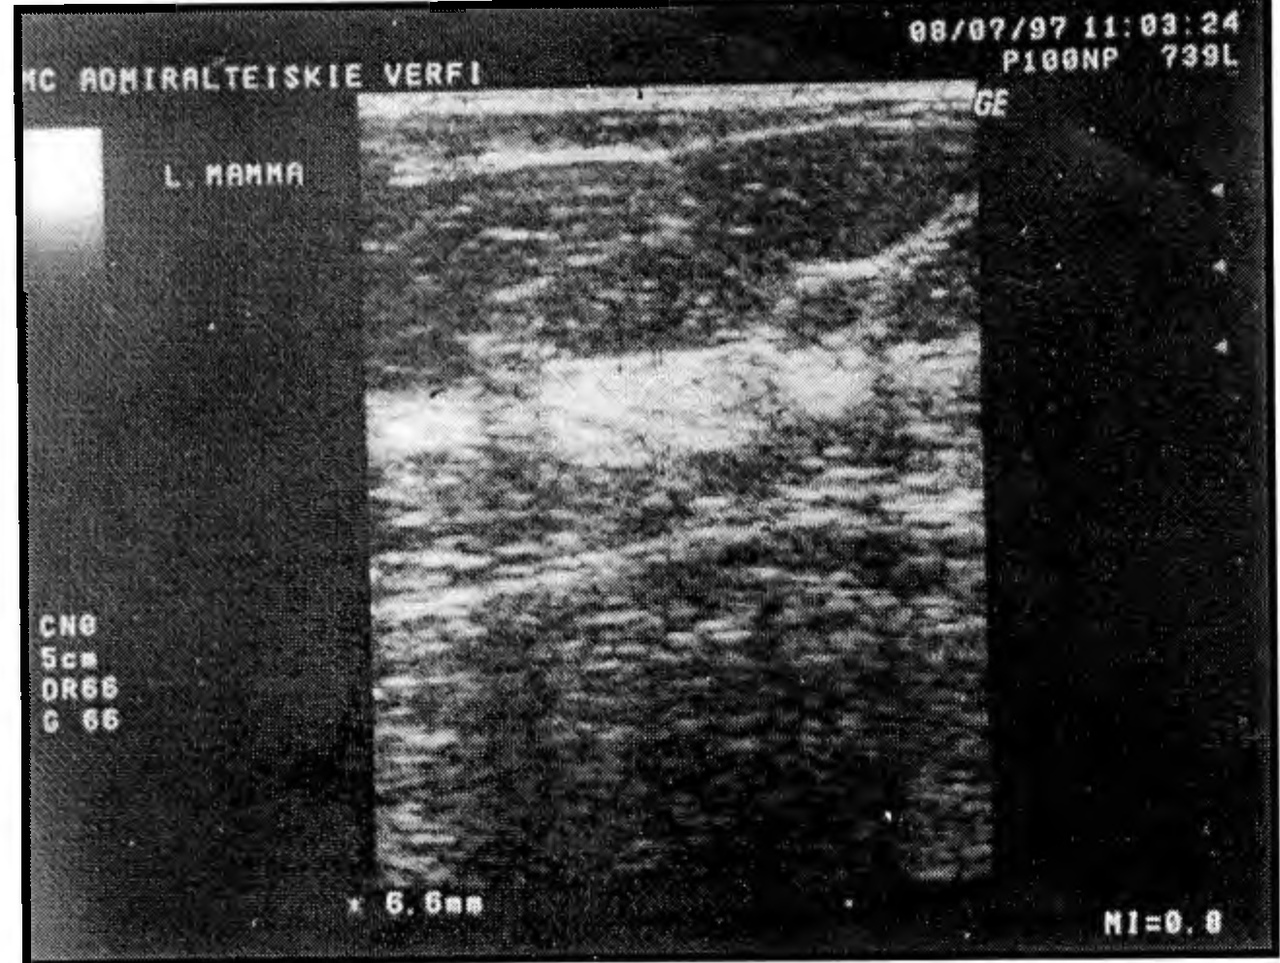

При фиброзном варианте основным эхосимптомом являются фиброзные изменения, проявляющиеся значительным повышением показателей эхоплотности, которые не соответствуют возрасту пациенток. В наших исследованиях эти изменения сочетались с утолщением слоя паренхимы молочной железы (рис. 8).

Рис. 8. Эхограмма фиброзного варианта диффузного ФАМ у пациентки 34 лет. Утолщение слоя железистой ткани до 16 мм. Показатели эхоплотности - значительно повышенные (41-43).